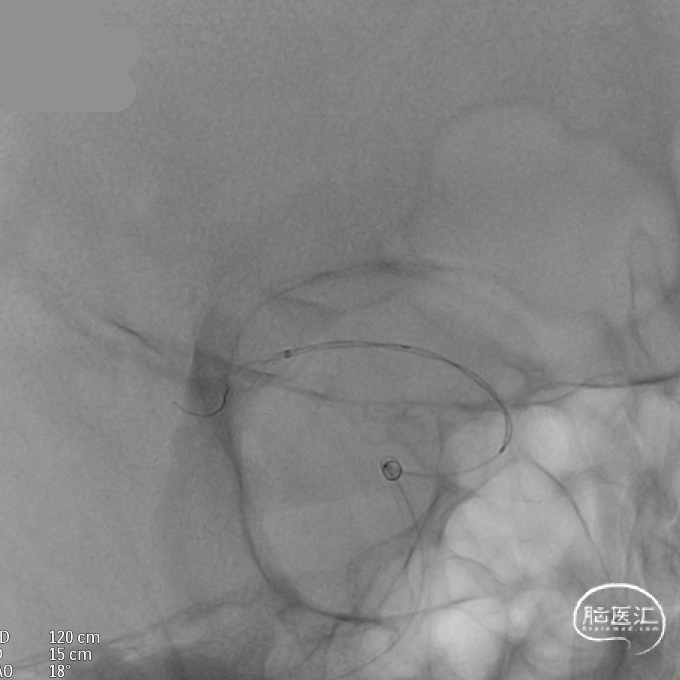

支架全部释放,调整张力,微导管通过支架,回收输送导丝。

支架内使用成襻微导丝进行按摩,使支架充分贴壁。

术后造影:支架充分覆盖动脉瘤瘤颈,贴壁良好,瘤体内可见造影剂滞留。

术后支架显影:定位精准,未覆盖颞前动脉及大脑前动脉。